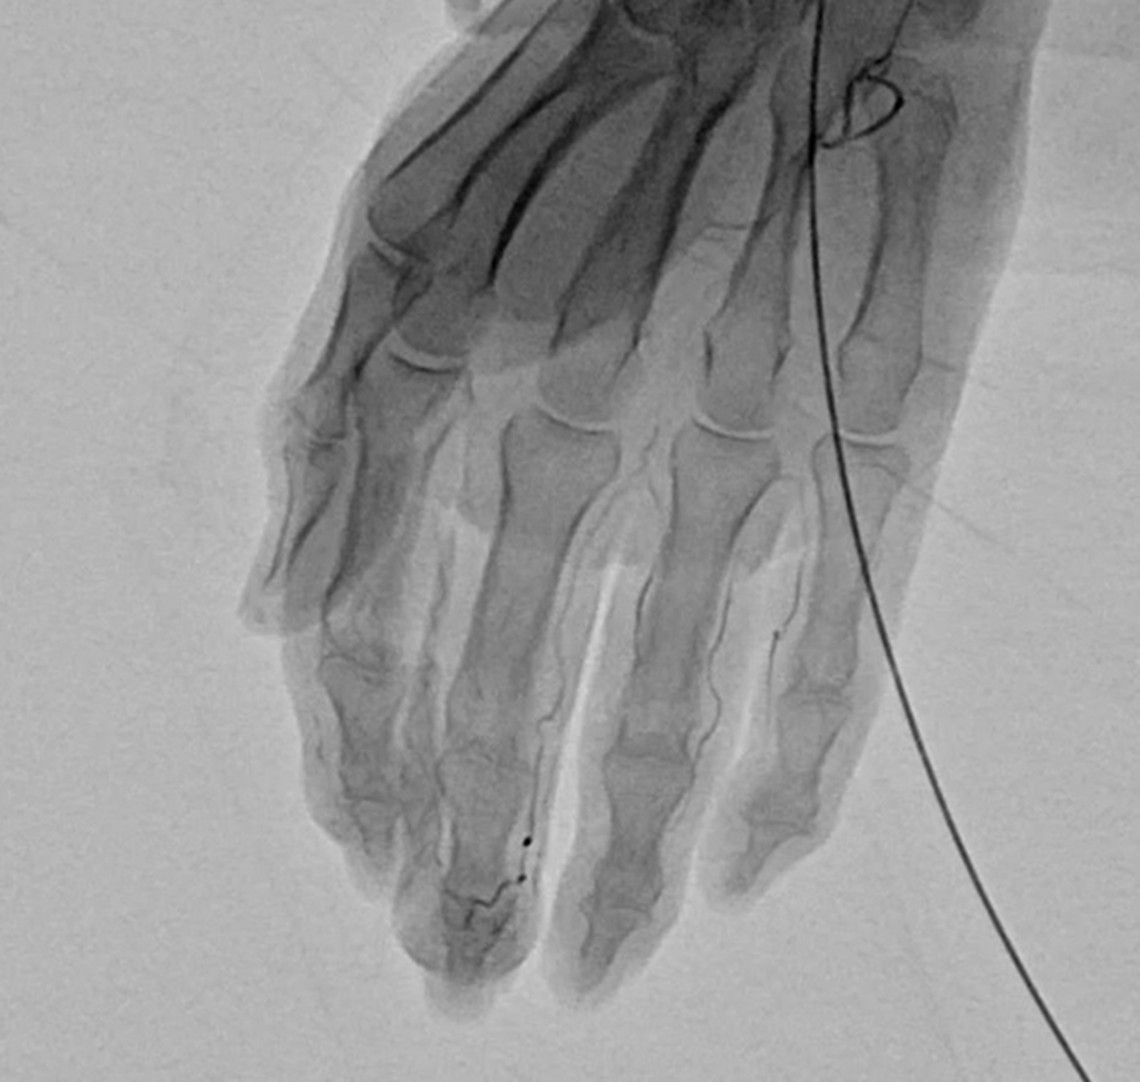

慢性的な痛みが続く部位には、異常な毛細血管(新生血管)=「モヤモヤ血管」が発生していることがあります。これは炎症や組織のダメージにより、けがや炎症が起きた場所の組織を修復しようとして、本来はないはずの場所に過剰に増えてしまった毛細血管です。画像検査で霧がかかったように見えることから「モヤモヤ血管」と呼ばれます。

血管の中に特殊な薬剤を注射して、異常な血管を塞いだり、消滅させることによって、痛みの根本的な治療をはかります。

細い針もしくは留置針をエコーで確認しながら動脈に挿入していきます。